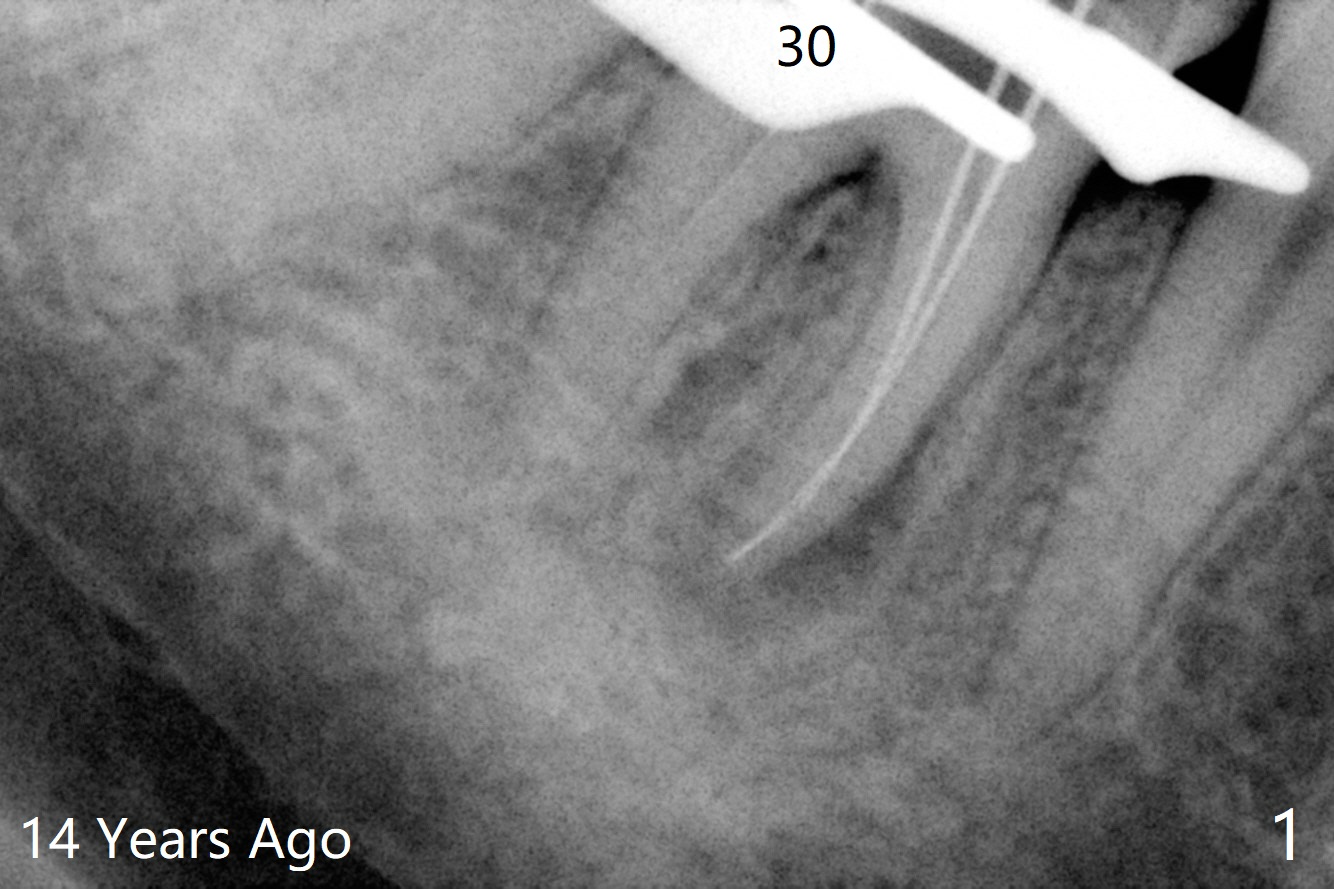

A 47-year-old woman with one carious tooth in her mouth (at #30) received RCT 14 years ago (Fig.1). The molar survives without crown for 3.5 years (Fig.2) and with crown for 8 years (Fig.3). The tooth has 2nd decays 10 years post crown (14 years post RCT, Fig.4 *). The crown dislodges 2 months later (Fig.5). Does the crown inadvertently reduce the longevity of the tooth simply hampering oral hygiene? After osteotomy until 4.5x10 or 13 mm IS drill with guide and 5 mm Bicon reamer free hand, place either 5x6 or 11 mm Bicon implant (Fig.6). Keep the black insertion plug to hold periodontal dressing or a provisional, which will be bonded to the neighboring tooth. Prepare PRFx1 for sticky bone around the not-so-stable implant. A 5x11.5 mm bone-level implant is planned by CT (Fig.7). Socket shield will be conducted to reduce buccal plate collapse. If the osteotomy depth is 10 mm due to limited mouth opening, place 4.5x6 mm Bicon implant. Otherwise 4.5x8 mm one. Return to Lower Molar Immediate Implant, Prevent Molar Periimplantitis (Protocols, Table), Trajectory II, Metronidazole Early Intervention Xin Wei, DDS, PhD, MS 1st edition 09/01/2019, last revision 11/10/2019